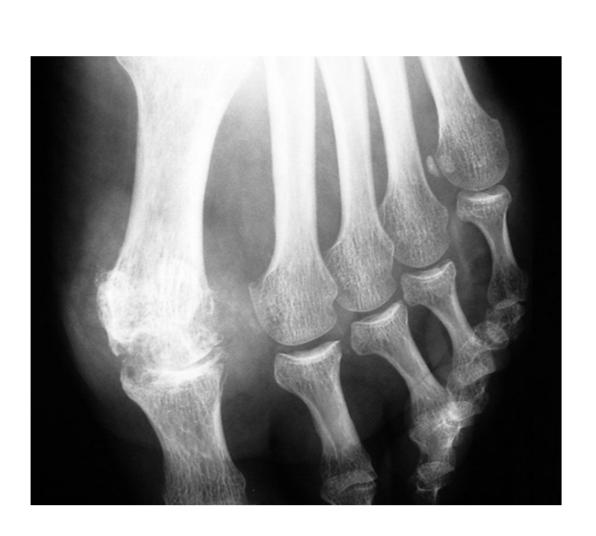

Goutte chronique

pincement global +condensation 1ere MTP

Érosions

Infiltration des parties molles

pincement global 1ere MTP

Érosions multiples

Tophus sous-cut